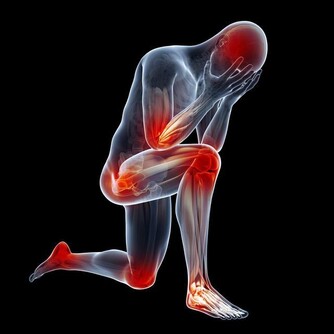

眾所周知,一旦尿酸高了,會引發全身性疾病,首當其衝的就是關節疾病,對於腎臟、血管等都會有不同程度的損害,還會影響血糖引發糖尿病等等。

如果尿酸高了,晚上睡覺時身體會出現下面幾種情況,千萬不要忽視!

4、腰疼

身體裡面的尿酸如果堆積很多,腎臟就會出現非常嚴重的負擔,容易導致腎結石問題出現,腎臟出現問題就會影響到腰部的健康,容易出現疼痛感覺,情況嚴重的話還容易導致失眠症狀出現,所以一定要特別注意。